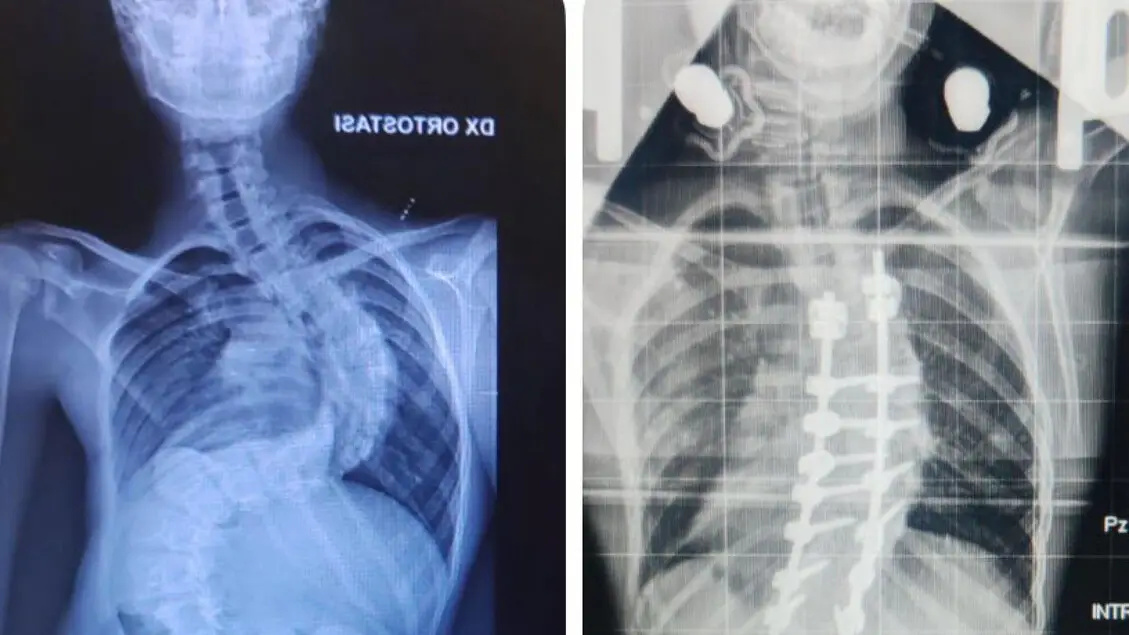

Grave scoliosi di 117 gradi, operato con successo 13enne a Bari

Natale a casa per adolescente dopo intervento equipe Chirurgia Vertebrale del Policlinico